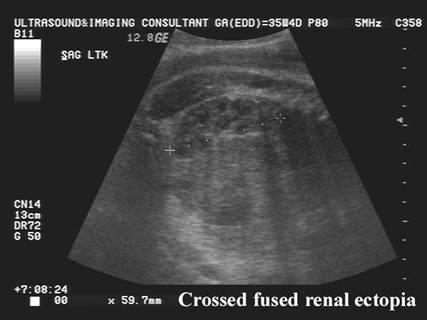

Cross-over fusion kidneys